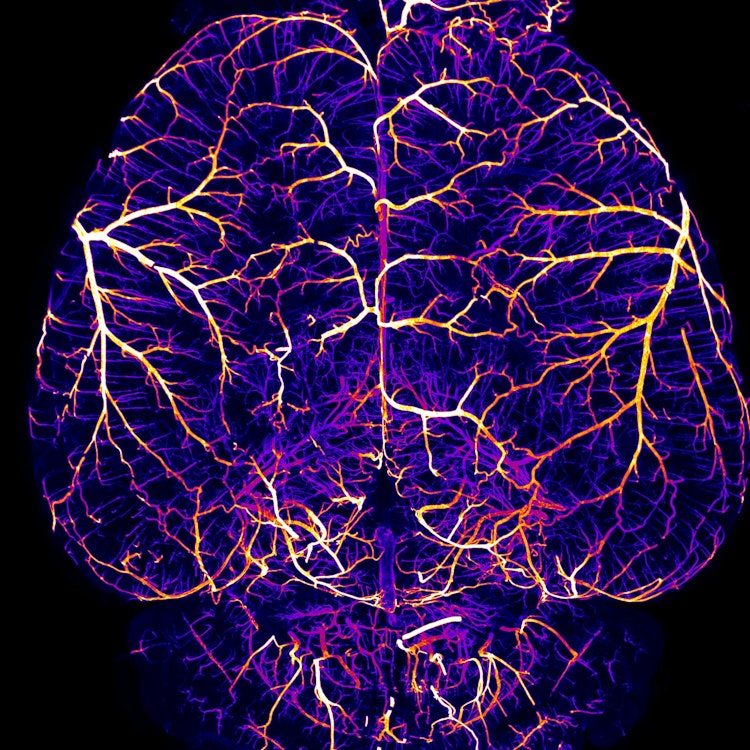

Recanalization is the mainstay of ischemic stroke treatment. However, even with timely clot removal, many stroke patients recover poorly. Leptomeningeal collaterals (LMCs) are pial anastomotic vessels with yet unknown functions. Utilizing a thrombin-based mouse model of stroke and the gold standard fibrinolytic treatment rt-PA, we here show that LMCs play a critical role in preserving vascular function in ischemic territories. We applied laser speckle contrast imaging, ultrafast ultrasound, and two-photon microscopy, to show that after thrombolysis, LMCs allow for gradual reperfusion resulting in small infarcts. On the contrary, in mice with poor LMCs, distal segments of recanalized arteries collapse and deleterious hyperemia causes hemorrhage and mortality. Accordingly, in stroke patients with poor collaterals undergoing thrombectomy, rapid reperfusion resulted in hemorrhagic transformation and unfavorable recovery. Thus, we identify LMCs as key components regulating reperfusion after stroke. Future therapeutic interventions should aim to enhance collateral function, allowing for gradual reperfusion of ischemic tissues after stroke.